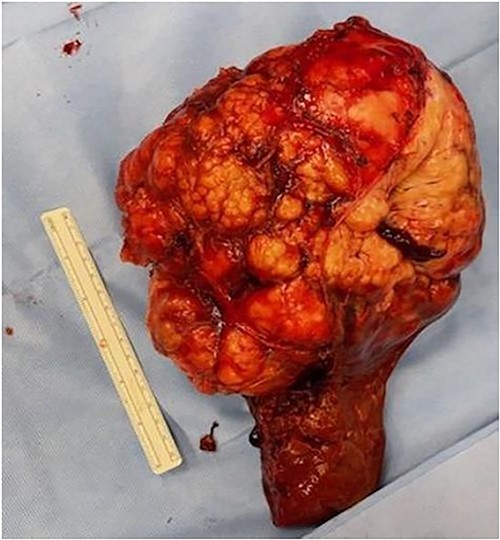

The patient underwent an exploratory laparotomy with right hepatectomy and cholecystectomy utilizing a low CVP strategy. An intrahepatic Glissonian approach was utilized and the right sided vascular inflow and outflow were transected during the parenchymal transection rather than extra-hepatically. Intraoperatively, blood loss was 750 mL, largely during parenchymal transection. A pringle maneuver was not used. The patient received intraoperative resuscitation with 1500 mL crystalloid, 500 mL 5% albumin, 1 unit of packed red blood cells (prbc) and 1 unit of autologous prbc via an intraoperative cell salvage device. Following removal of the specimen, intraoperative ultrasound was utilized to survey the remaining left liver; however, no other concerning lesions were identified. The patient was managed on the surgical floor postoperatively with an unremarkable postoperative course, requiring 1 unit of prbc on postoperative day (POD) 4 because of a hemoglobin level of 6.9 gm/dL with an appropriate and sustained response. The patient was subsequently discharged home on POD 5. The final surgical pathology was consistent with meningioma, and all surgical margins were negative > 1 cm (Fig. 2).